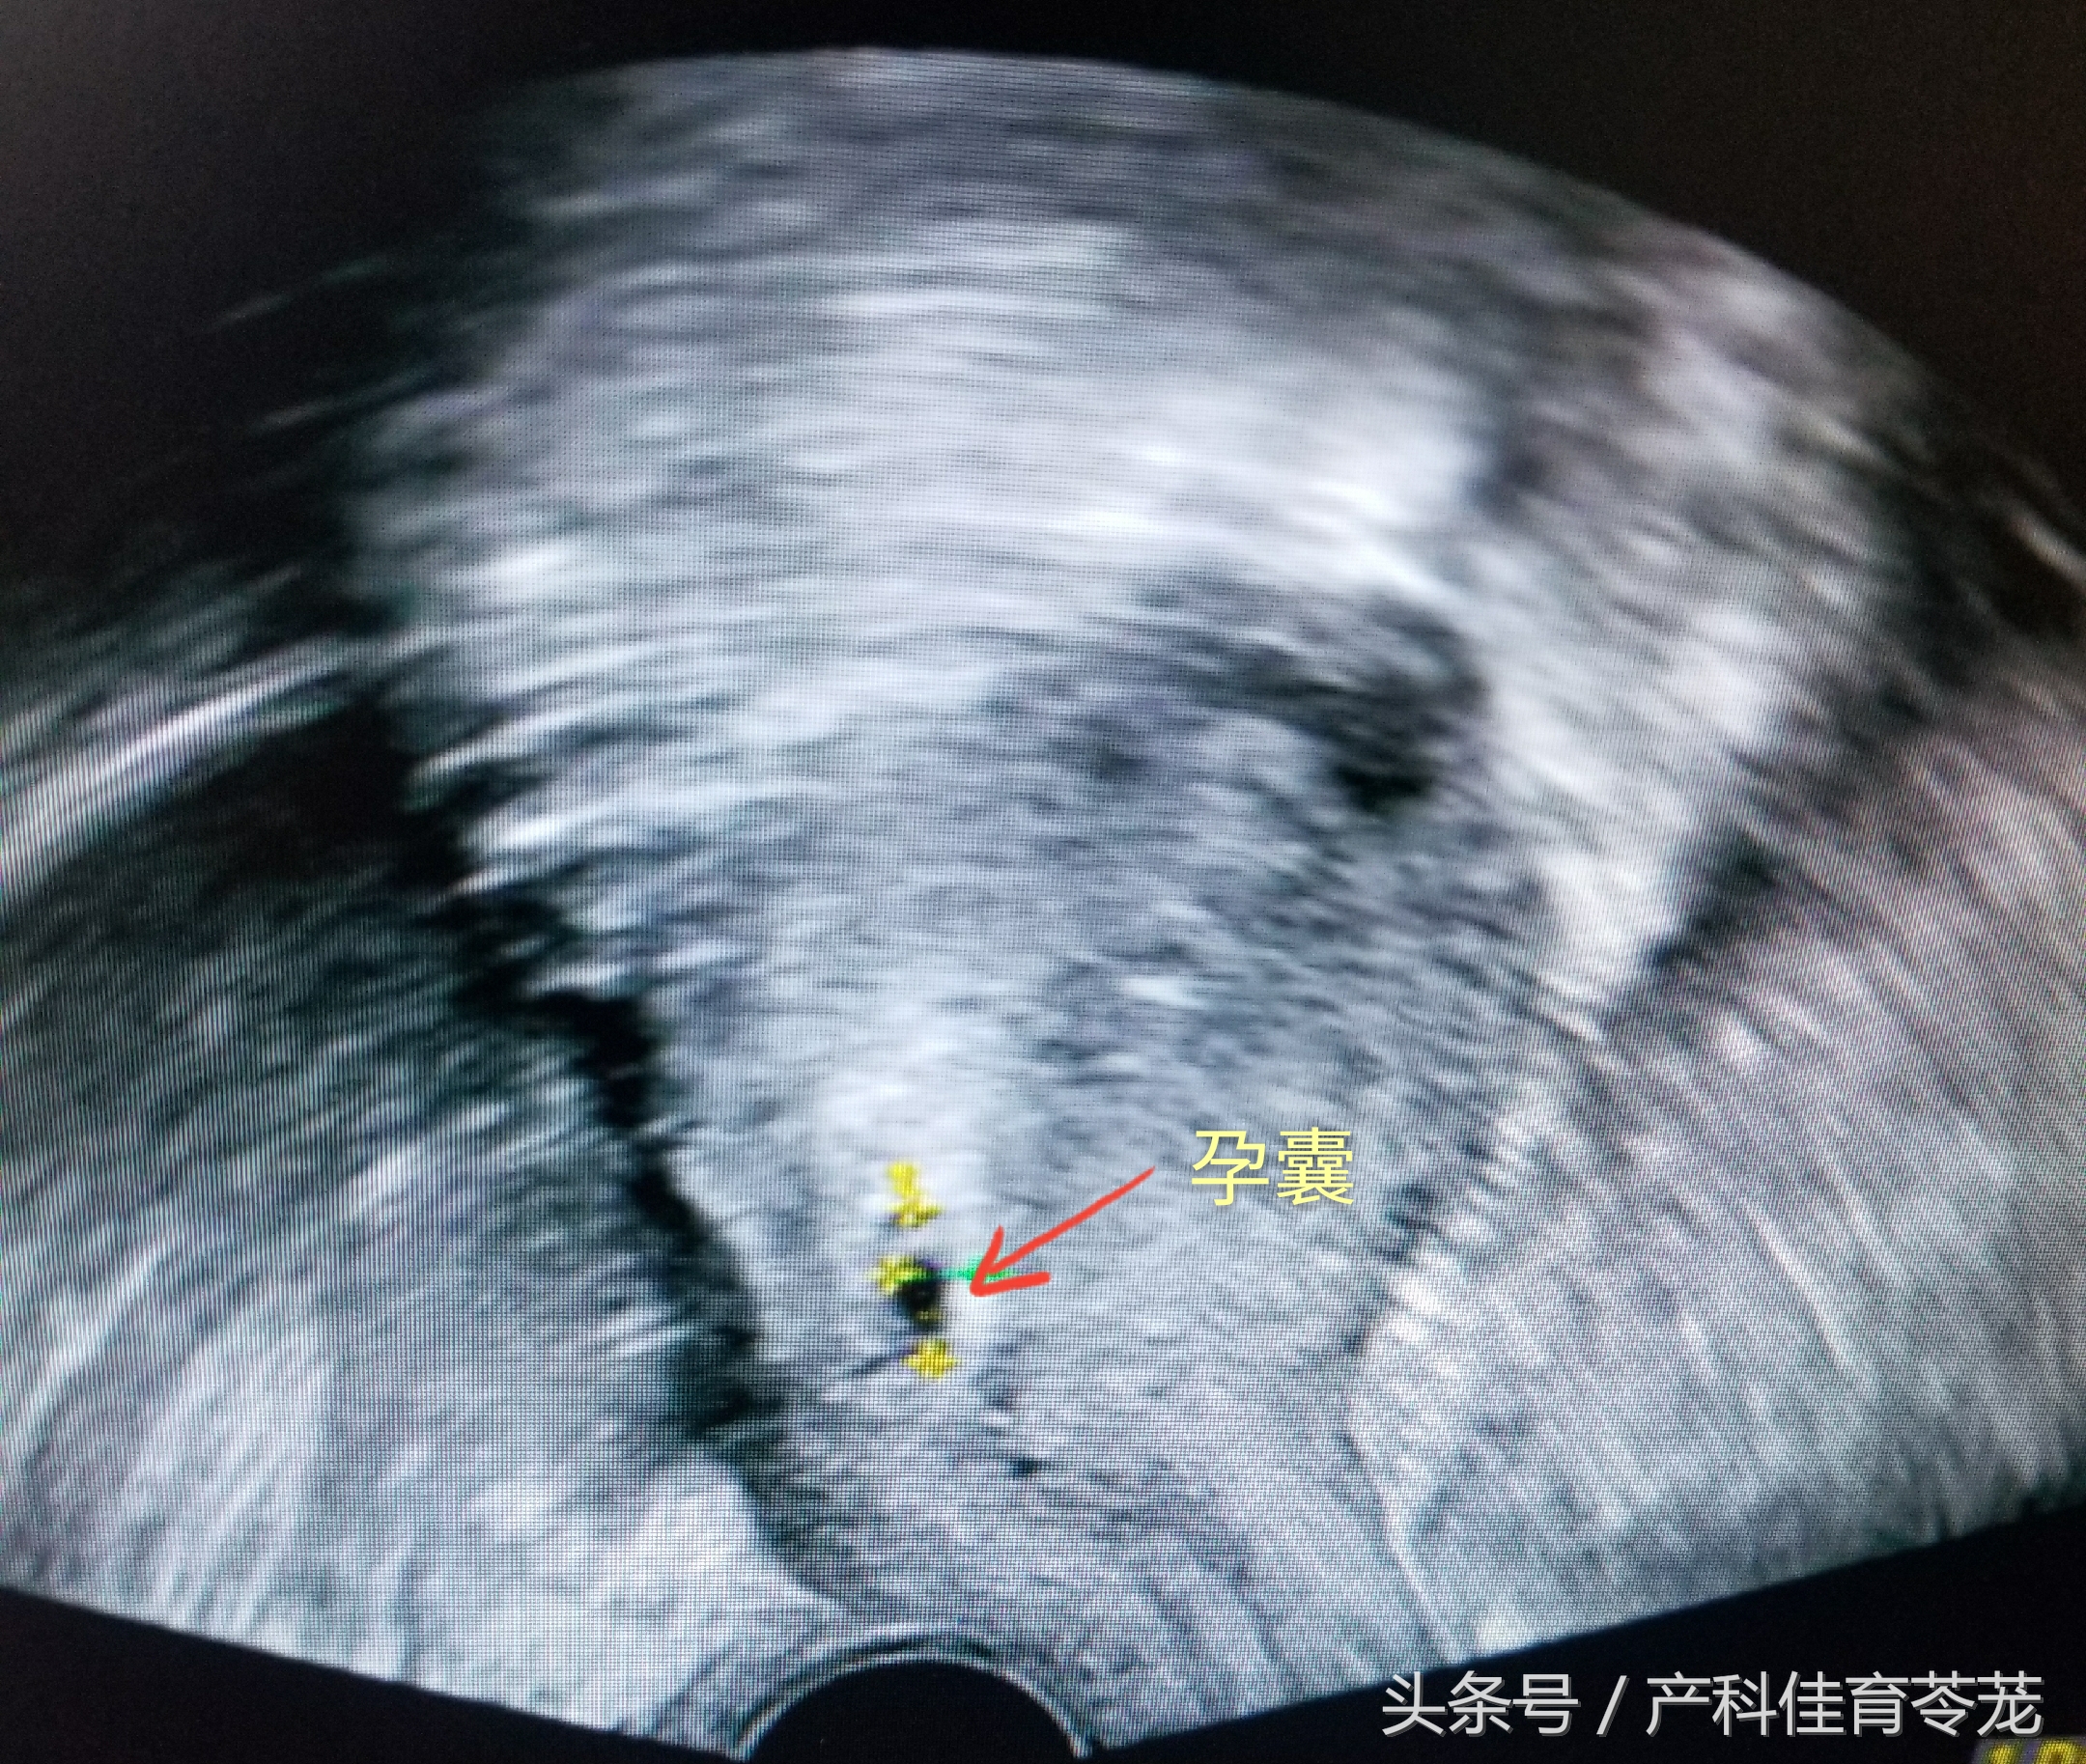

医生告诉她可疑瘢痕妊娠,告知继续妊娠下去非常危险。她又去了另一家医院做了阴道B超,结果提示宫内早孕,只是胎囊位置偏低:

医生建议她继续观察,最后顺利怀孕到孕39周,剖宫产分娩,母子平安。